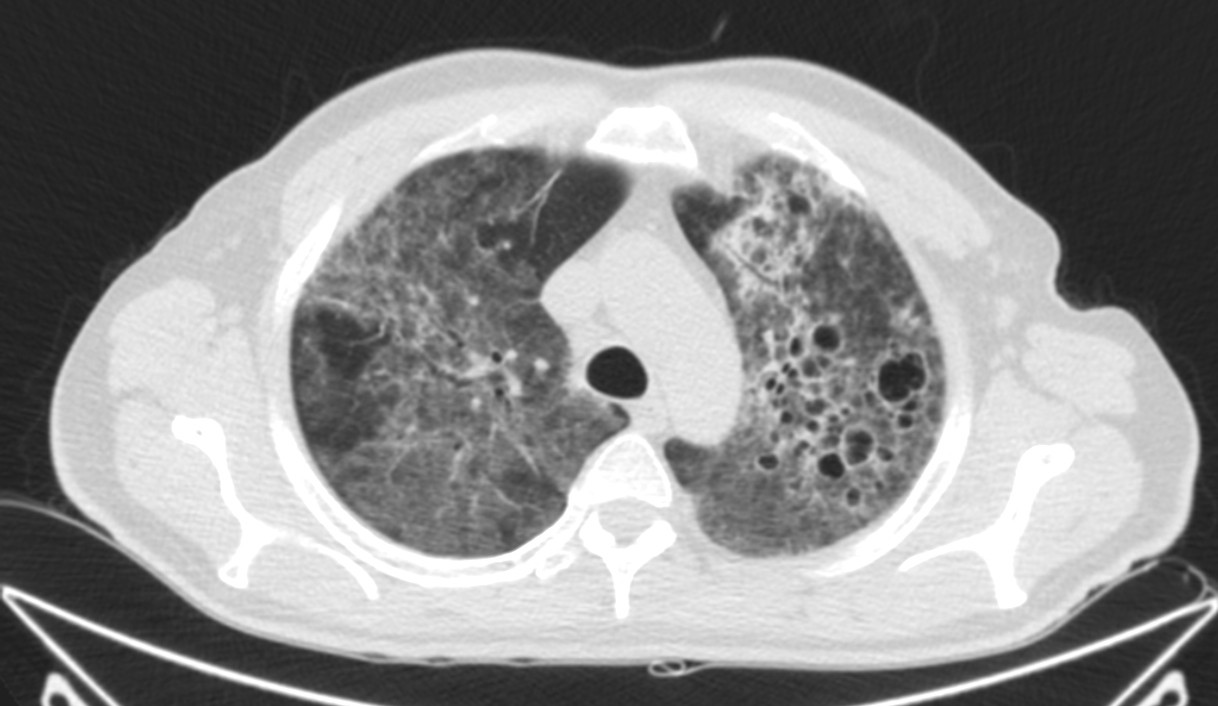

Describamos los hallazgos:

TAC: Vidrio deslustrado difuso y perihiliar frecuente, infiiltrado reticular, consolidaxión y patrón de árbol en brote, engrosamiento de septos, patrón en empedrado, derrame pleural, quistes.